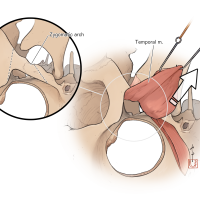

監修:谷川 緑野 / 札幌禎心会病院脳卒中センター

監修:太田 仲郎

監修:永田 雄一